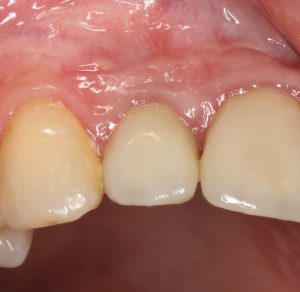

Вот клиническая картина через 4 месяца после ранее проведенной имплантации с остеопластикой:

Как видишь, коллеги из недалекой дружественной страны не осилили снятие швов. Мне это не нравится, хотя и объясняет, почему люди готовы ехать за тыщи километров ради 20-минутной операции удаления зуба мудрости.

Ну хорошо. Швы сняли. Делаем разрез. Обрати внимание, что после всех проведенных операций у нас остается очень небольшой по ширине слой жевательной слизистой оболочки:

Мы встретились как старые друзья. Честно признаюсь, я очень переживал. Я ожидал увидеть какую-нибудь жуть, утраченную кость, периимплантит, разрушенный вхлам протез и всё такое. Но… всё оказалось не так плохо: